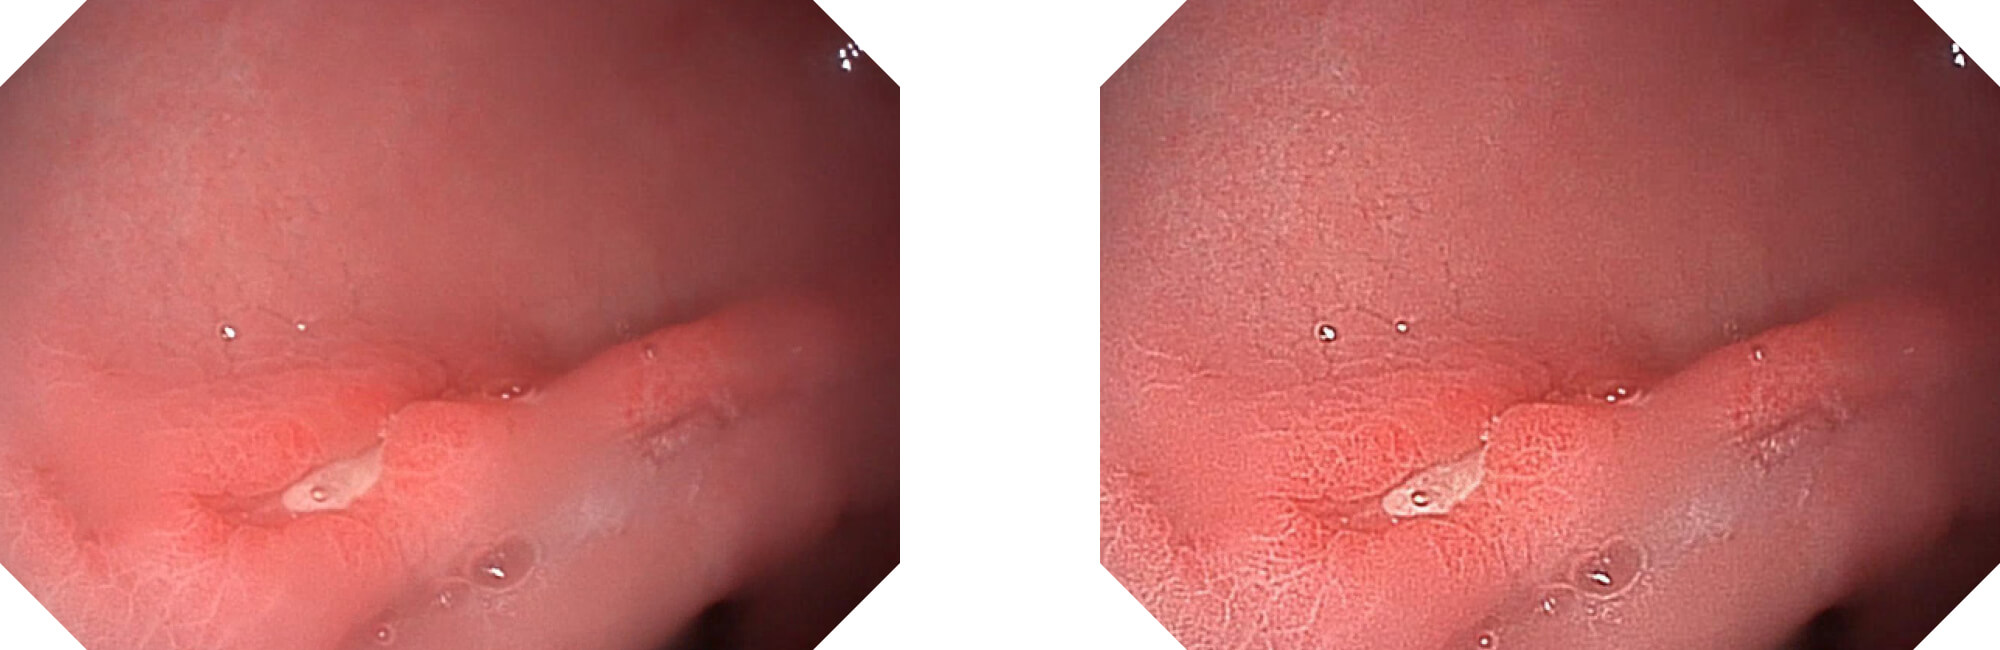

利用了血红蛋白在不同波长吸收下系数不同的原理,设计的一种光学域滤波和数字域滤波结合的染色技术,既保证了图像亮度,又可增强黏膜血管的对比度,充分凸显早期病变的细微结构变化,为临床疾病的观察诊断提供更丰富的参考信息。